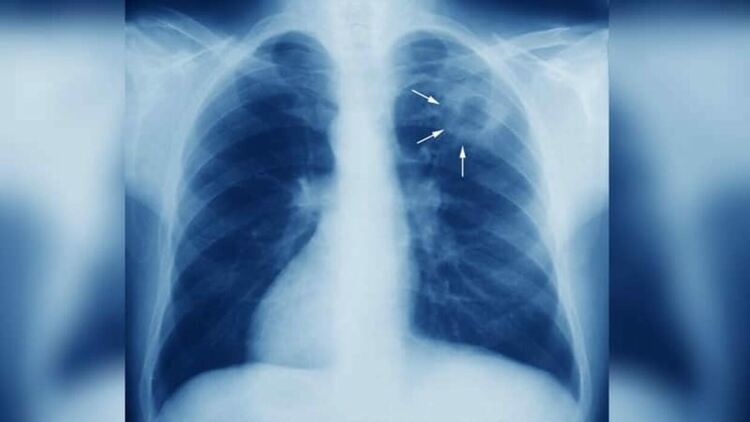

Нов случай на туберкулоза в Кърджали,заболелите в региона се увеличават тревожно

Нов случай на туберкулоза бе регистриран от здравните власти в област Кърджали през изминалата седмица.С него общият брой на установените пациенти с „жълтата гостенка” стават 11,сред които и едно дете.

Туберкулозата (на латински: Tuberculosis), разговорно наричана също охтика или особено в литературата „Жълтата гостенка“, е хронично протичащо специфично възпалително заболяване, което засяга предимно белите дробове, но може да засегне и централната нервна система, лимфните съдове, храносмилателната система, костите, ставите или кожата.

Класическите симптоми на активната туберкулозна инфекция са хронична кашлица с примесени с кръв храчки, температура, нощно потене и загуба на тегло. В миналото наричали туберкулозата „охтика“, заради загубата на тегло при инфектираните.